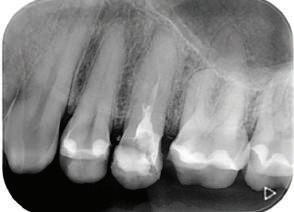

Dental Tribune Bulgarian Edition / октомври 2022 г.18 воначалния план. Тези пробле ми бяха адресирани чрез допъл нителна поръчка на алайнери с торк контрол и зададено екст рудиране на задните зъби с цел установяване на добри оклузал ни контакти в дисталните об ласти, като бяха предвидени и оптимизирани атачмънти с контрол над корените за корекция на ангулацията на макси ларните резци (фиг. 8). Резултати от лечението Панорамната рентгено графия след ортодонтското лечение показа благоприятна паралелна позиция на съседни те зъби, подходяща за поставя не на имплант в областта на #22, както и конвергенция на ко рените на зъби #44 и 45 (фиг. 9), но преценихме, че няма да от деляме допълнително лечебно време за коригирането ѝ поради факта, че пациентката бе мно го доволна от постигнатия до момента резултат. След при ключване на лечението бяха постигнати отлични взаимо отношения клас I при мола рите и канините, а срединни

съвпадаха. Върху им

ти и клас II ластици е устано вено, че осигурява достатъч на дистализация без промяна на лицевата височина.23 Както се видя от цефалометричния анализ, точно това бе постиг нато и в представения случай като се има предвид, че лице вата височина остана същата като първоначалната. Предвид леката тенденция към дистал Фиг. 8a–e Поръчаните допълнителни алайнери. Фиг. 9 Панорамна рентгенография след края на лечението. Фиг. 10a–c Странични (а и с) и фронтална интраорални снимки след края на ортодонтското лечение и поставянето на импланта (b). Зъб #12 все още не беше протезиран. Фиг. 11а и b Оклузални снимки след ортодонтското лечение. Фиг. 7a Фиг. 8a Фиг. 7d Фиг. 8d Фиг. 9 Фиг. 10a Фиг. 10b Фиг. 10c Фиг. 11bФиг. 11a Фиг. 7b Фиг. 8b Фиг. 7e Фиг. 8e Фиг. 7c Фиг. 8c Фиг. 7a–e Интраоралната ситуация по време на лечението. клиничен случай с алайнери

Dental Tribune Bulgarian Edition / октомври 2022 г. 19 на отворена захапка е устано вено, че финалното адаптиране и подобряване на оклузалните контакти се установяват след повече от три месеца след лече нието.24 Следователно подобря ване на ситуацията и плътни оклузални контакти се очак ват след края на лечението. Що се отнася до избора за замест ване на липсващия латерален резец с единичен имплант и протезирането му, установе но е, че това е най-често при лаганата лечебна алтернати ва.25 Съседните зъби остават интактни и следователно най голямото предимство на този подход е съхраняването на здра ви зъбни структури. Изборът ни на лечебен план бе базиран на детайлна мул тидисциплинарна диагноза и планиране, а те категорично са ключови за постигане на оп тимални индивидуални резул тати при пациенти